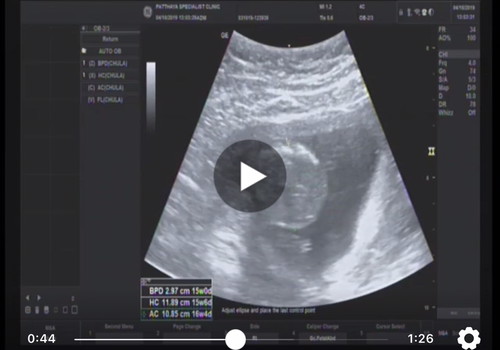

สอบถามแม่ๆหน่อยคะ ว่าดูตงไหนว่าได้กี่วีคคะ

วิธีดูนะคะ